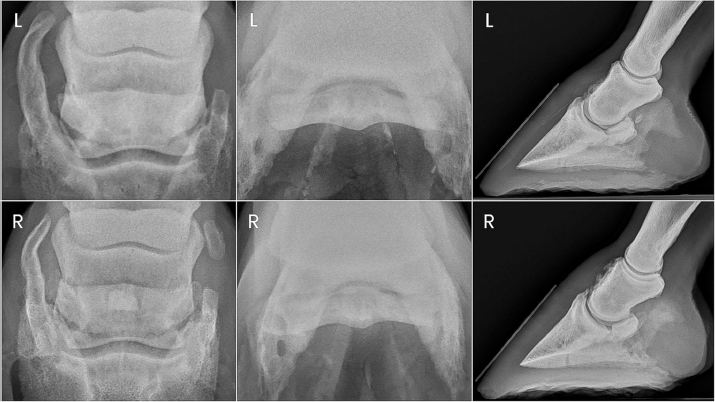

Fig. 2. Preoperative radiographs of the digits of horse 2.

Two years after donation, the gelding progressed to displaying a grade 4/5 right forelimb lameness. This lameness was eliminated with diagnostic anesthesia of the right palmar digital nerves at the level of the proximal interphalangeal joint and replaced by a grade 3/5 left forelimb lameness. The left forelimb lameness was then eliminated with diagnostic anesthesia of the left palmar digital nerves in a similar fashion. PDN was performed as a salvage procedure to maintain pasture soundness. Preoperative radiographs showed severe bilateral navicular bone degeneration with focal mineralization of the DDF tendon bilaterally (Fig. 2).